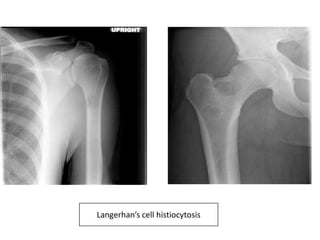

Langerhan’s cell histiocytosis

• X ray-

• Well defined, lytic lesions.

• Cortical involvement may elicit periosteal reaction.

Langerhan’s cell histiocytosis.

Osteolytic lesion of skull.